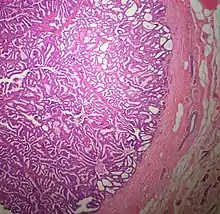

The microscopic histopathology of typical PDCIS lesions (refer to adjacent high-power photomicrograph) prepared with a hematoxylin and eosin stain consists of mammary ducts that have papillary fronds (i.e. thin, finger-like or leaf-like structures) lined with one or several layers of neoplastic, columnar-shaped epithelial cells (i.e. tall, narrow cells with their nuclei close to the site of their ductal attachment).[4] The fronds have branching fibrovascular cores. Epithelial cells lining the fronds' inner surfaces commonly form solid, cribriform (i.e. large nests of cells perforated by many rounded, variably sized spaces), or micro-papillary patterns. There may be a second population of epithelial cells lining the papillae that have abundant clear cytoplasm in addition to the usual neoplastic epithelial cells which line the papillae. These cells, which are not myoepithelial cells, have been termed globoid cells.[7] They have eosinophilic cytoplasm (i.e. pink or red cytoplasm due to its uptake of eosin stain).[6] PDCIS tumors with these cells have been termed dimorphic variants of PDCIS.[3] Myoepithelial cells are typically present at the periphery of the fronds but absent within the involved ducts.[4][7] The presence of a fibrous capsule and/or absence of peripherally located myoepithelial cells are strong indicators that the tumor is an ESP rather than a PDCIS.[3] PDCIS tissues may also contain areas of "Comedo-type necrosis", i.e. areas where dead cells have accumulated.[6]